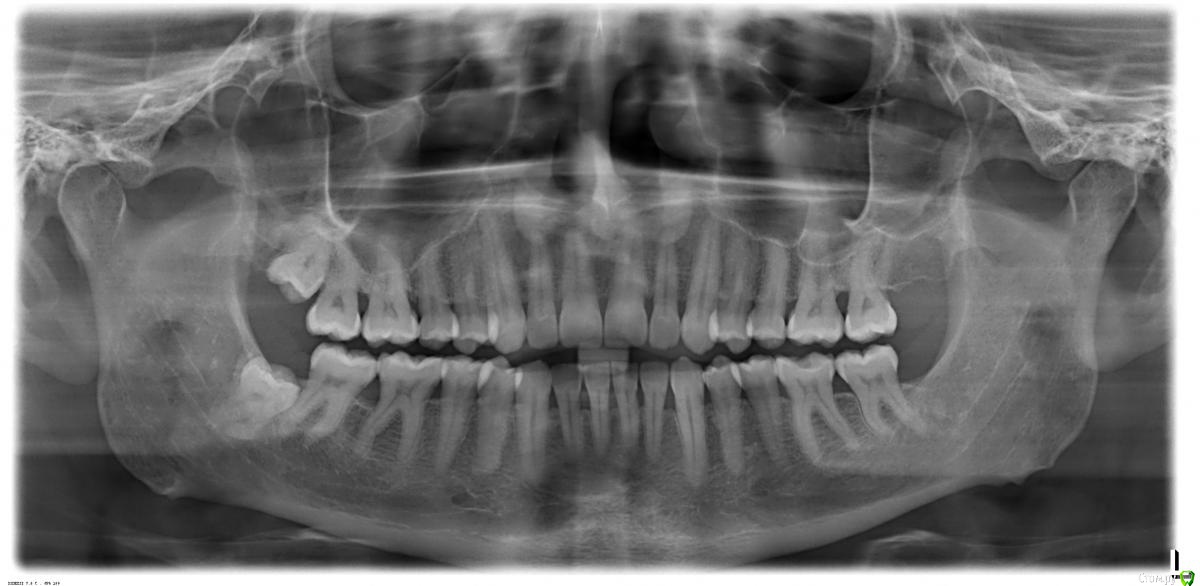

Поставили диагноз пародонтит, убыль кости, рецессия десны в области моляров.

Кровоточивости и подвижности нет, гигиена в норме. Есть ощущение зуда межу 6-м и седьмым зубом с одной стороны, причина которого стоматологом не обнаружена. Временно помогает ершик и ирригатор.

Ситуация с деснами длится довольно давно, если ухудшается, то медленно.

Добрый вечер. На данном этапе важнее всего качественная домашняя гигиена. Применение ирригатора систематически будет большим плюсом. Проф гигиена  и осмотр парадонтолога обязательно каждые 4-6 месяцев как стоматолог скажет при очном осмотре, и дальше смотреть динамику.  Парадонтит есть, но ничего страшного не увидела